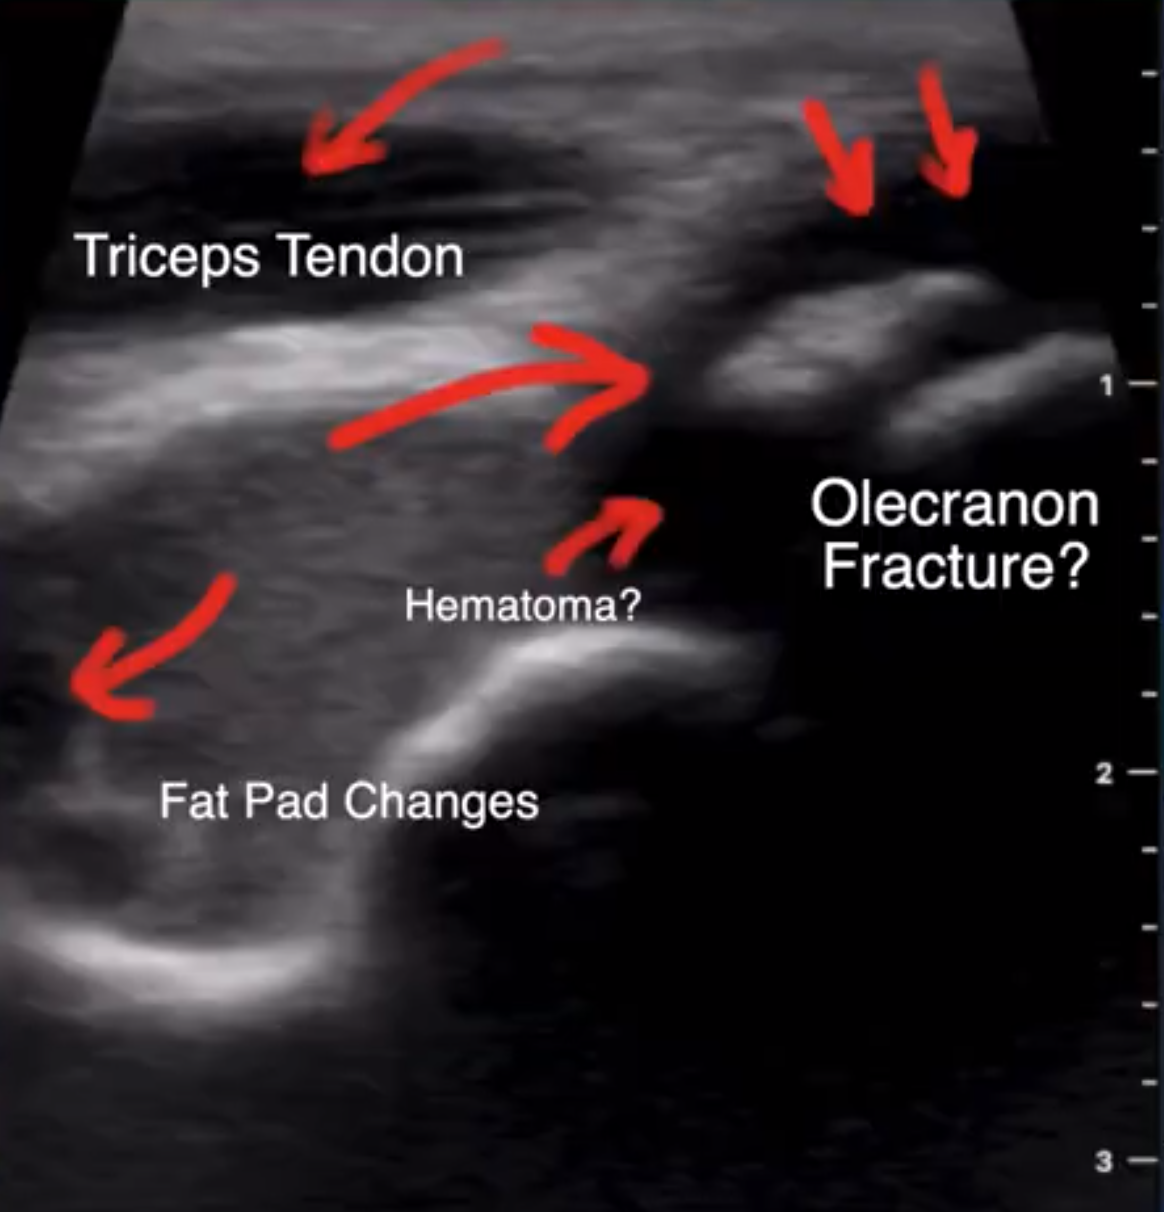

The ultrasound showed an abnormal signal to the fat pad as well as to the tip of the olecranon. The hypo-echoic or darker area around the olecranon is consistent with fluid but not a normal signal for this area. There is a piece of bone (large arrow), or hyper-echoic area, in the center of the hypo-echoic area. You can see lines through this fragment. Based on the history of the injury and the ultrasound imaging a referral to orthopedic surgery was recommended.

We repeated the ultrasound and added the left side for comparison. Both elbows showed a hypo-echoic area surrounding a hyper-echoic area consistent with a bone fragment at the tip of the olecranon. This would most likely be a congenital abnormality and not a fracture. I learned that even though the ultrasound finding is abnormal it may be normal for that person. It is easy to image the other side for comparison. This example showed that this boy injured his right elbow but it was not fractured and letting him slowly progress on his own with physical therapy to restore mobility was the course of action needed.